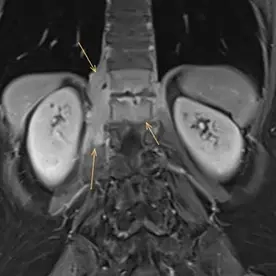

In der angefertigten MRT des LWS und des Abdomens zeigt sich eine kräftige T2w-Signalanhebung in den Wirbelkörpern BWK 12 und LWK 1 mit Irregularitäten der Abschlussplatten (Bild 1). Die angrenzende Psoasmuskulatur zeigt sich auch signalalteriert, betont auf der rechten Seite (Bild 2). Bei der Kontrastmittel-Unterstützer-Untersuchung zeigt sich ein kräftiges Enhancement in den Wirbelkörpern und der angrenzenden Muskulatur (Bild 3). Besonders auf der rechten Seite zeigen sich zudem auch abszessartige Formationen (Bild 4).

Der Befund ist vereinbar mit einer Spondylodiszitis von BWK 12/LWK 1 mit Absenkung in den Musculus psoas beidseits, rechtsbetont, differentialdiagnostisch ist hier an eine Tuberkulose als Ursache zu denken.